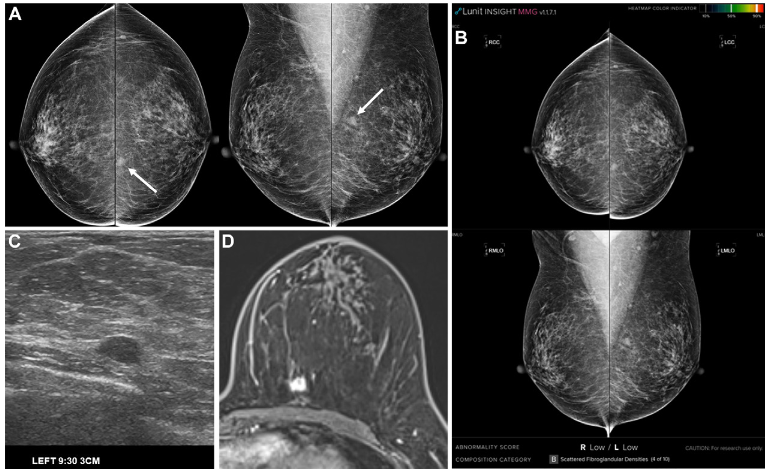

Figure 2: A 42-year-old woman with dense breasts had an invasive ductal carcinoma in the left upper outer quadrant missed by AI due to a low AS. Confirmed post-surgery (luminal subtype).